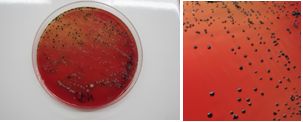

Las colonias presuntivas de A. actinomycetemcomitans se identificaron por la presencia de una estructura semejante a una estrella en el interior de las colonias con una lupa estereoscópica (Fig. 1), técnica de coloración de Gram, prueba de catalasa (+) y MUG negativa (4-Metilumbeliferil-β-D-galactósido) para investigar la fermentación de la lactosa.

Las bacterias anaerobias pigmentadas (Porphyromonas y Prevotella) se identificaron por la formación de pigmento (Fig. 2). Para su diferenciación, se observaron también mediante fluorescencia bajo luz ultravioleta (360 nm) donde las colonias de P. gingivalis no fluorescen y las de P. intermedia si lo hacen (Fig. 3). En caso de dudas se realizó la identificación con pruebas bioquímicas para anaerobios a través del kit API®.